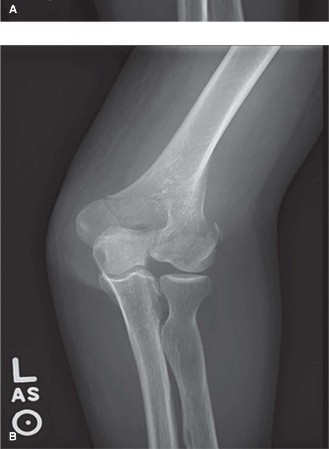

A 54-year-old, right-hand-dominant, high school principal presents to the emergency department with severe left elbow pain after a fall onto the extremity which she sustained earlier that morning while walking her dog. She notes pain with any movement of the elbow, and her clinical examination finds this to be a closed

injury with an intact median, radial, and ulnar nerve examination. Injury radiographs are shown in Figure 6–10A and B.

The correct answer is (C). These images show an intra-articular fracture involving both the medial and lateral columns of the distal humerus with no articular portion remaining in continuity with the diaphysis. Multiple radiographic views may be necessary in order to make this determination, especially when there is minimal displacement. A CT scan can be useful for both classification and operative planning purposes. Multiple classification systems are used to describe these fractures, and below are figures showing two of the more commonly cited: the AO/OTA classification in Figure 6–11A and the scheme described by Jupiter and Mehne in Figure 6–11B.